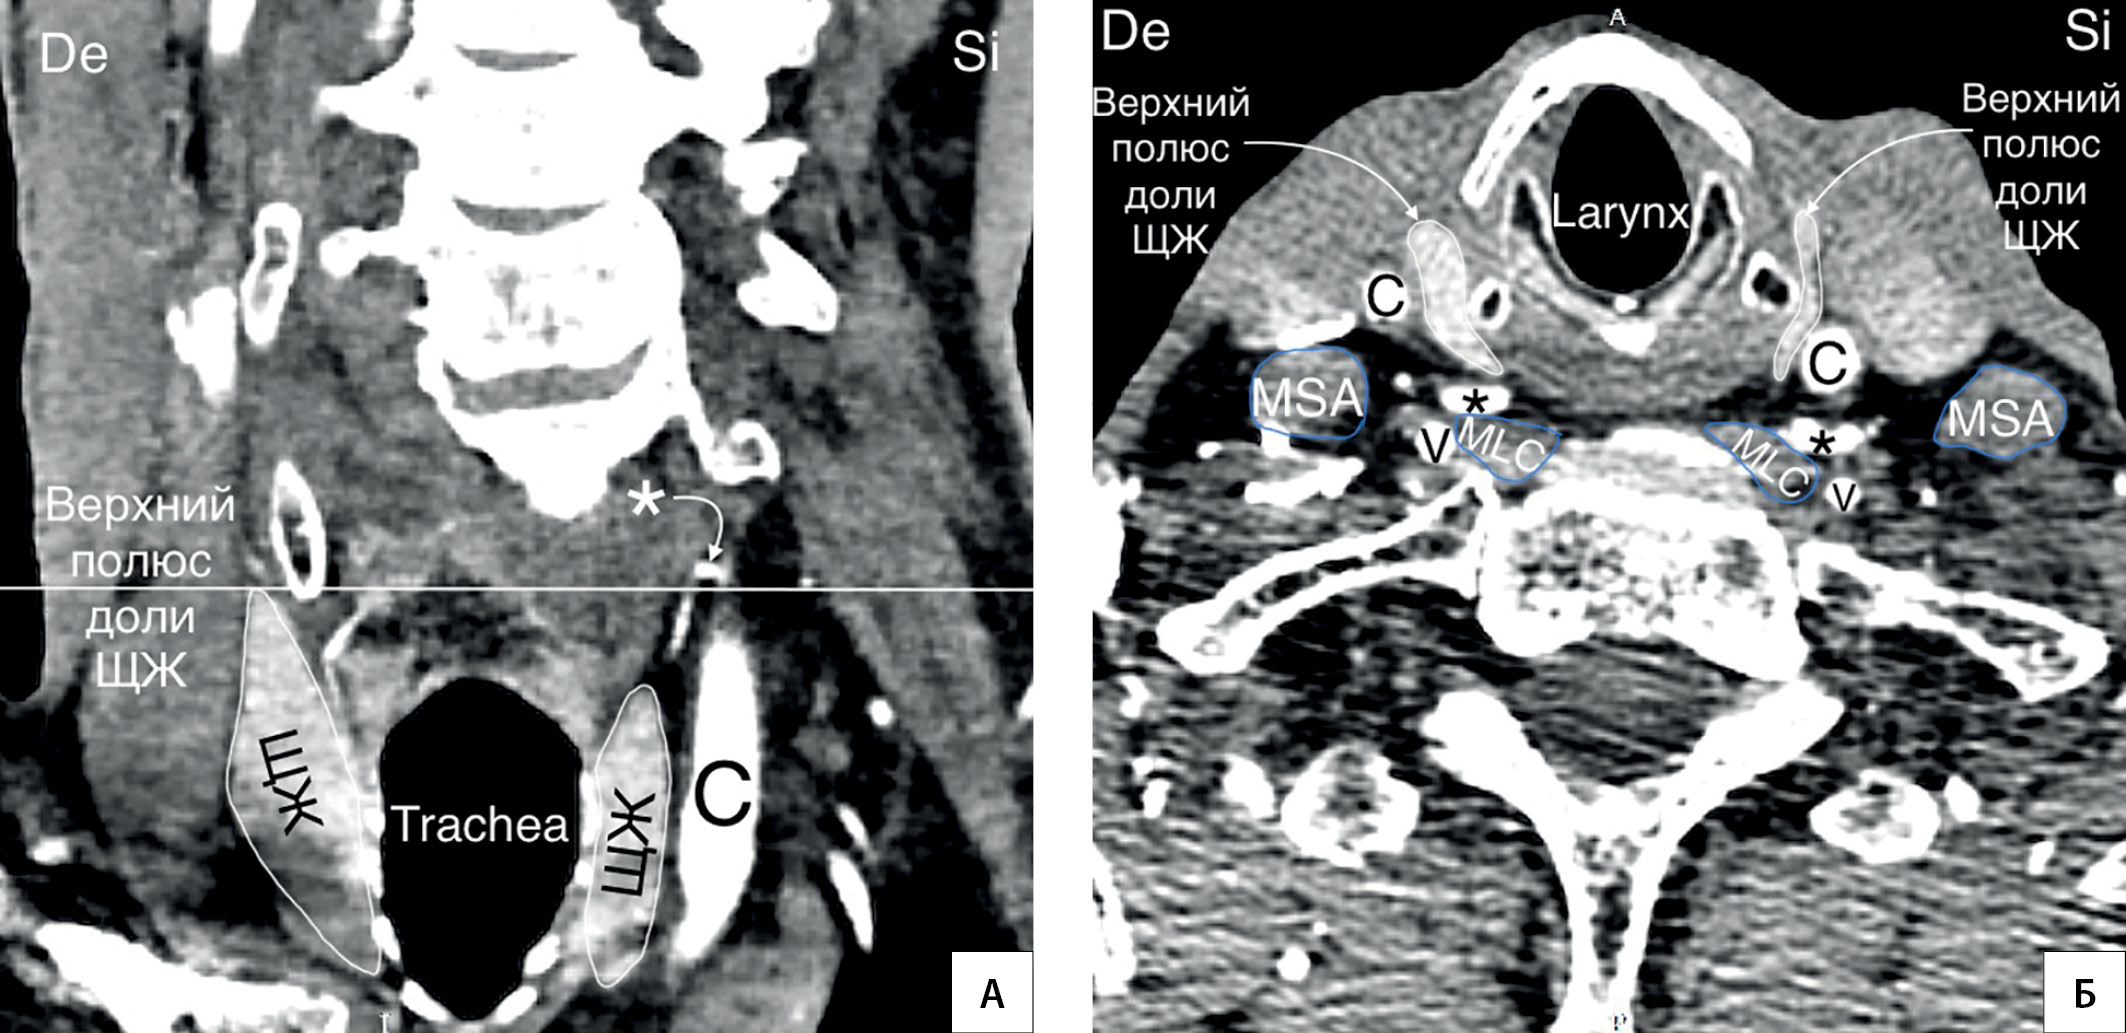

6. Рисунок 6. Колено НЩА располагается на уровне средней трети доли ЩЖ. А — КТ-ангиограмма (сагиттальный срез); Б — КТ-ангиограмма (горизонтальная плоскость); * — колено НЩА; C — a. carotis communis; V — a. vertebralis; MSA — musculus scalenus anterior; MLC — musculus longus colli; De — dextra; Si — sinistra. | |